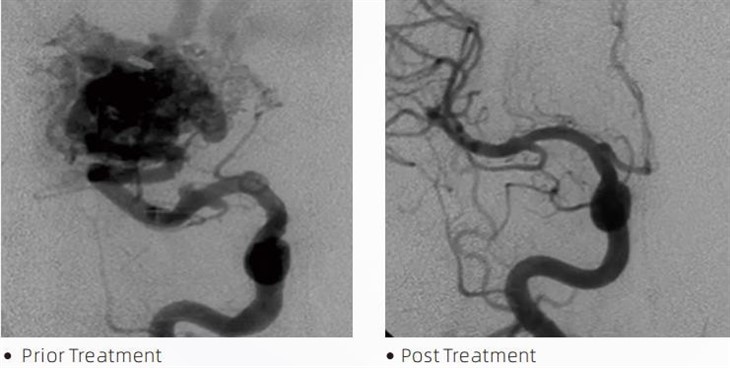

溶岩ティッカー塞栓接着剤は、脳動脈瘤、動静脈奇形、腫瘍などの症状を治療するための低侵襲処置中に介入神経放射線科医によって使用される医療機器です。 Lava 塞栓接着剤は、安全性、使いやすさ、有効性の点で、医療専門家と患者の両方に複数の利点をもたらします。 溶岩は血管を迅速かつ効率的に密閉することができます。 このプロセスでは、接着剤を標的の血管に直接注入し、接着剤が重合して硬化してキャスト状の塊となり、動脈瘤や奇形を満たします。 その後、病変への血流を効果的に遮断し、病変の破裂を防ぎ、永久的な損傷や脳卒中のリスクを軽減します。 溶岩には溶岩-12、溶岩-18、溶岩-34が含まれます。 各製剤は、特定の臨床ニーズを満たすように設計されています。 溶岩-18は一般的に使用される標準配合です。 Lava-34 は高流量容器用の高粘度接着剤です。 一方、Lava-12 は粘度が低く、流動性が高いため、遠位の微小血管が可能になります。 これらのオプションを使用すると、介入神経放射線科医は適切な Lava 製剤を選択して、最適な結果を確保できます。 Lava の最も注目すべき特徴の 1 つは、その非粘着性です。 この物質は、標的領域に到達するまで安定性を保つように特別に配合されています。 この特性は、溶岩塞栓接着剤が動脈内に正確に配置され、周囲の組織に付着したり結合したりすることなくそこに留まることができることを意味します。